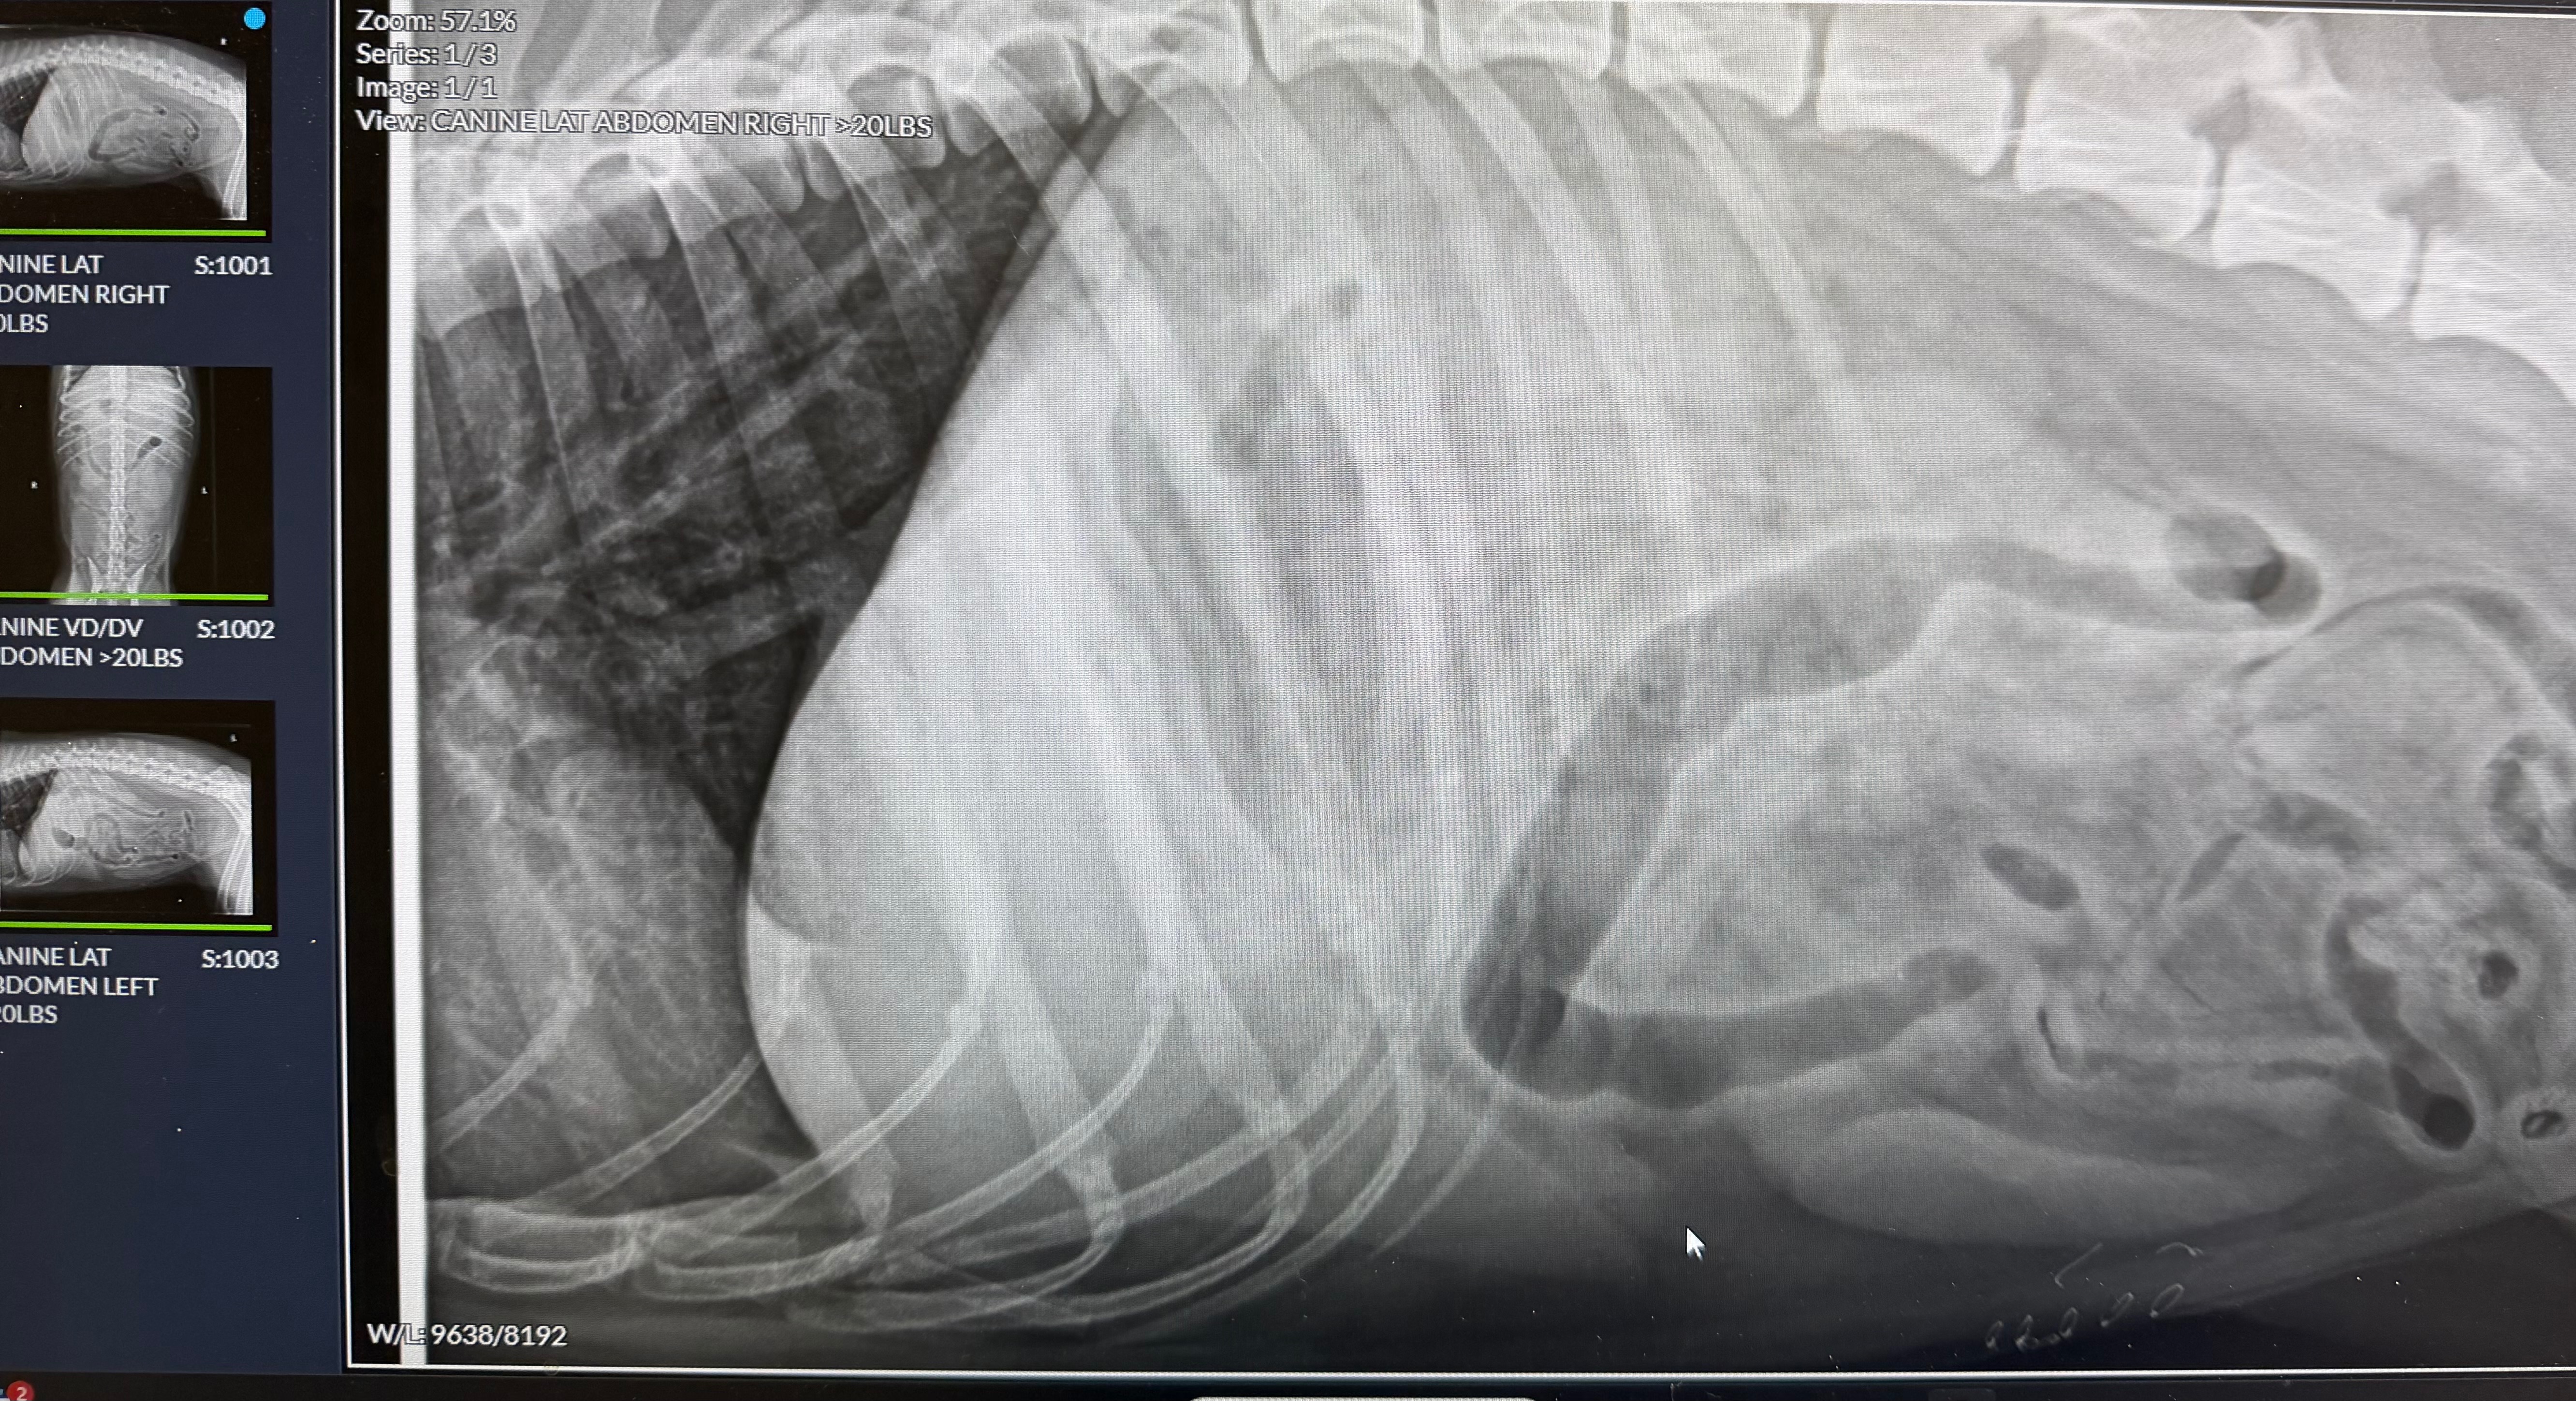

Recently, Remi got into some chocolate and ate bones she wasn’t supposed to, which caused severe pancreatitis. She’s currently in the emergency veterinary hospital, receiving IV fluids, pain medication, anti-nausea meds, and ongoing blood work and x-rays. Unfortunately, she’s not eating yet, and her condition is still uncertain.